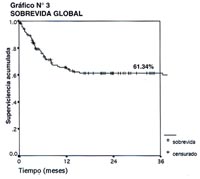

En el Gráfico N°3, se consigna la sobrevida global de los 169 pacientes con diagnóstico de Linfoma Gástrico tratados en el INEN en el periodo 1,995-2,000 con un seguimiento a 3 años, el cual es del 61.34%.